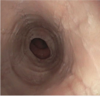

5

something wrong?

Eosinophilioc esophagitis

. Kid in clear capsule eosinophilic esophagitis = associated with dysphagia, food impaction, esophageal rings, strictures, furrows; increased eosinophils on biopsy